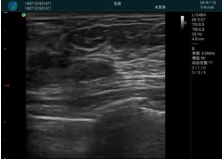

清晰顯示腺體內(nèi)低回聲快影,邊界清晰,包膜較光滑